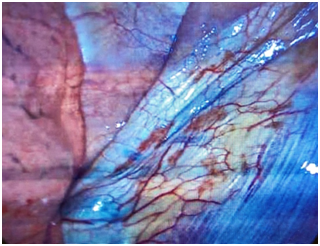

The patient underwent robotic single-incision laparoscopic surgery (SILS) resection of endometriosis, ovarian cystectomy, lysis of adhesions, and cystoscopy by Minimally Invasive Gynecologic Surgery (MIGS) team. After completion of the patient’s pelvic surgery, the thoracic surgery team performed bilateral video-assisted laparoscopy surgery (VATS) with assistance from the MIGS to help identify suspicious lesions. Intraoperative evaluation revealed thoracic endometriosis confined to the pleura of the lungs and the diaphragm. These lesions were resected via electrocautery (Figures 1–3). No parenchymal lung lesions were identified. The patient had an uncomplicated recovery and postoperative phase. Upon discharge the patient was started on oral contraceptive pills (OCPs). Based on the clinical presentation and intraoperative findings the patient was diagnosed with thoracic endometriosis.

Figure 2 Lesions on the right pleural surface.